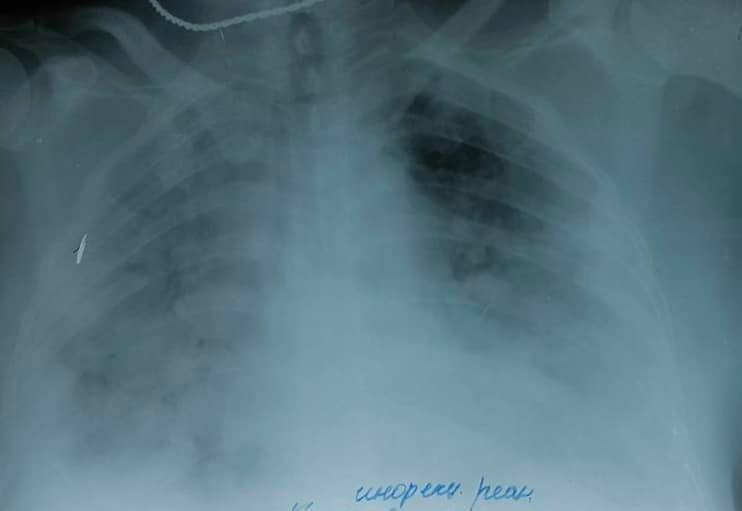

"Основное самое тяжелое осложнение сегодняшнего гриппа – тяжелые внегоспитальные вторичные пневмонии", – отметила Голубовская.

У больных наблюдаются осложнения гриппа - тяжелые внегоспитальные вторичные пневмонии Фото: facebook.com/ogolubovska